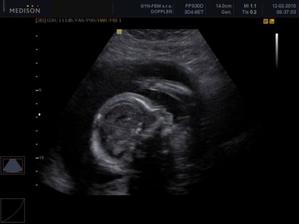

18.12. NT screening (šíjové prosvícení). Odpovídáme 11+5tt a mimi měří 5,2cm. Vše je OK. Komplet výsledky budu mít 28. 12., kdy jdu do poradny, ale kdyby bylo něco špatně hned budou volat ….. nikdo nevolááá 🙂)))